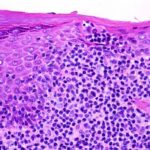

Mycosis Fongoïde =التفطر الكمئي